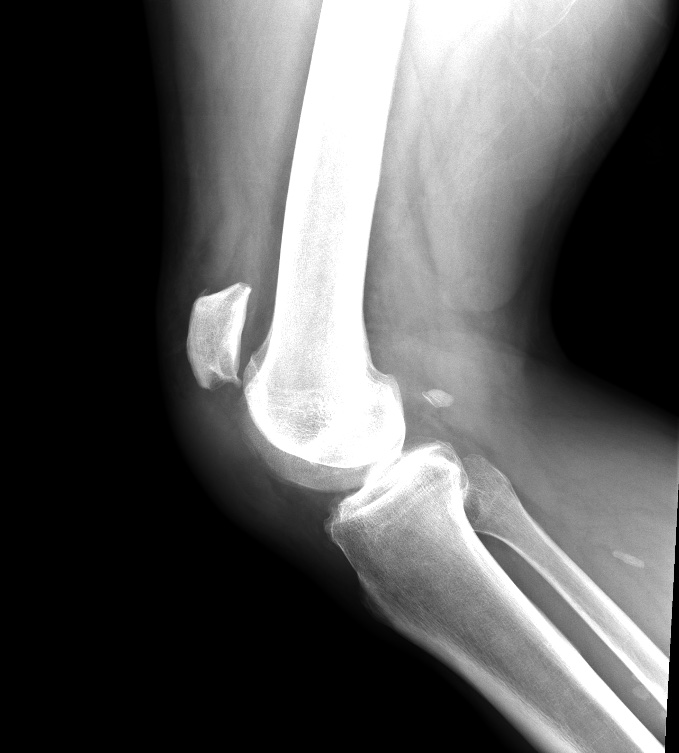

What’s the Diagnosis? Gepost op 11 oktober 2019 door netwerkvsseh What’s the Diagnosis? @emdaily.cooperhealth.org Dit delen: Delen op X (Opent in een nieuw venster) X Share op Facebook (Opent in een nieuw venster) Facebook Delen op LinkedIn (Opent in een nieuw venster) LinkedIn E-mail een link naar een vriend (Opent in een nieuw venster) E-mail Afdrukken (Opent in een nieuw venster) Print Vind-ik-leuk Aan het laden... Gerelateerd